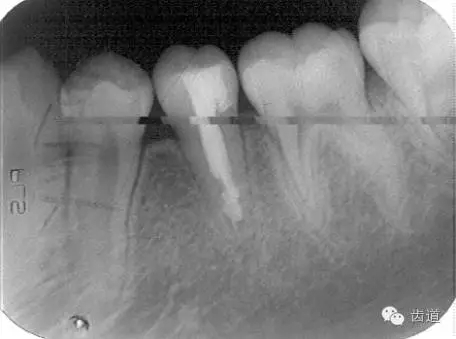

術(shù)后

術(shù)前

術(shù)后199日

術(shù)后1084日